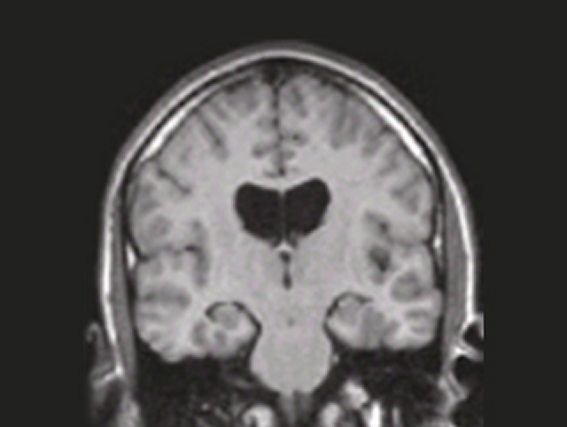

정상 뇌 영상 치매 환자 뇌 영상

정상뇌

치매 환자